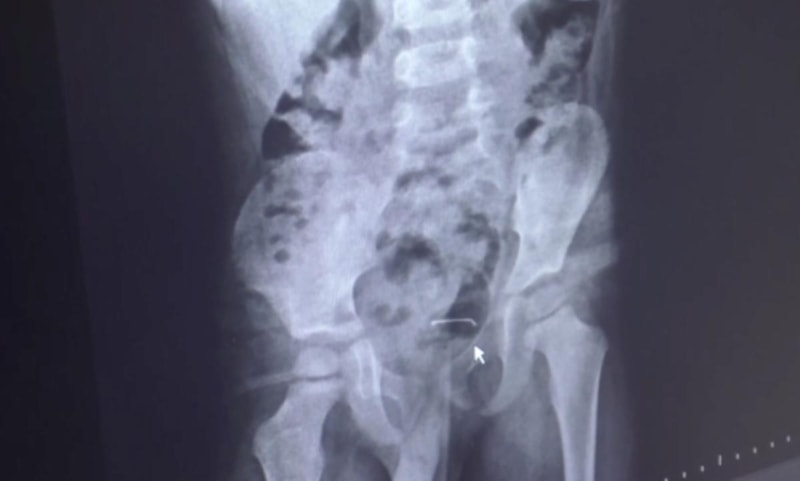

Karın ağrısı şikayeti bulunan çocuğun çekilen röntgeninde, mesane duvarında metal cisim olduğu tespit edildi.

Uzun bir süre çocuğun vücudunda kalan 3 santimetre civarındaki toplu iğnenin, mesane duvarına yapıştığı belirlendi.